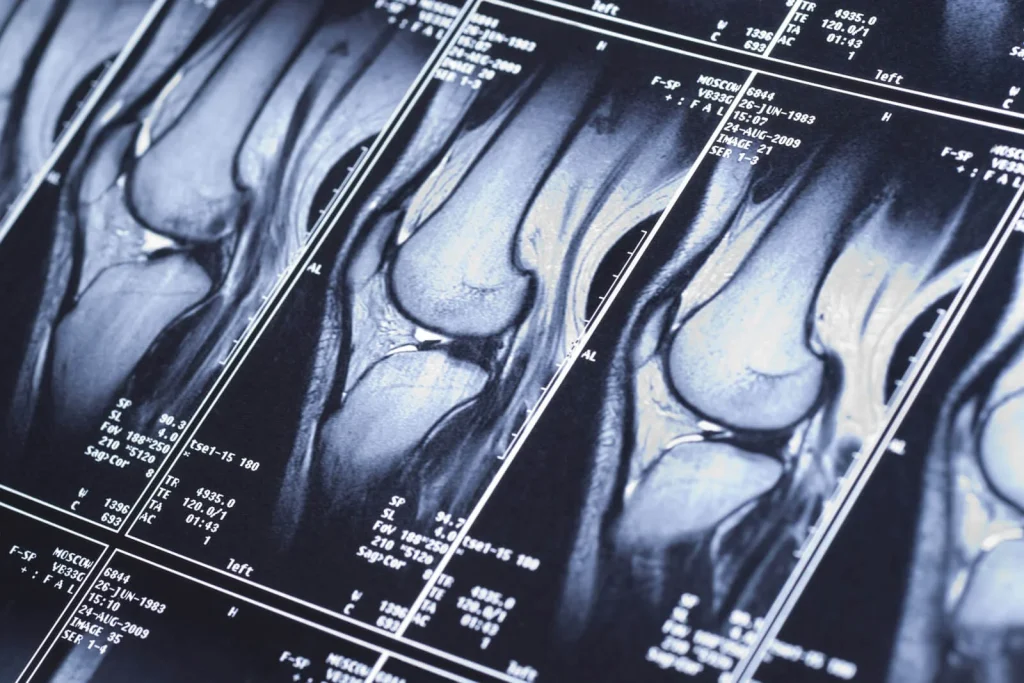

Коли суглоби дають про себе знати больом, обмеженням рухливості або незрозумілим хрускотом, звичайного огляду лікаря часто буває недостатньо. Для постановки точного діагнозу необхідна детальна візуалізація внутрішніх структур. У таких випадках лікарі все частіше призначають МРТ суглобів, яка стала золотим стандартом у діагностиці патологій суглобів. Більш детально про переваги та показання до цього обстеження можна дізнатися на сторінці медичного центру за посиланням: https://tovpollar.org/mrt-suhlobiv/.

На відміну від рентгена або УЗД, МРТ суглоба дозволяє одночасно оцінити стан кількох типів тканин. Метод дає чітке зображення не лише кісток, а й хрящів, м’язів, зв’язок, сухожиль, менісків та навколосуглобових сумок. Це робить його незамінним для виявлення таких проблем:

- Колінний суглоб: Діагностика розривів менісків, зв’язок (передньої та задньої хрестоподібних), пошкоджень хряща, тендиніту.